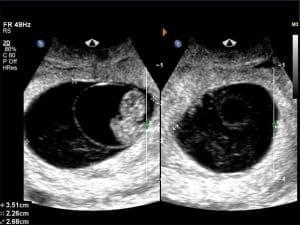

Learn how to assess and diagnose various umbilical cord abnormalities through sonography. This course covers key topics including cord length, cysts, coiling, two-vessel cords, vasa previa, and more. Gain insights into the importance of these conditions, their potential risks, and how ultrasound plays a critical role in early detection and management of complications during pregnancy.

Describe the clinical significance of abnormalities of the umbilical cord size, shape and vascularity.

Apply ultrasound findings to detect clinically significant changes in the umbilical cord.